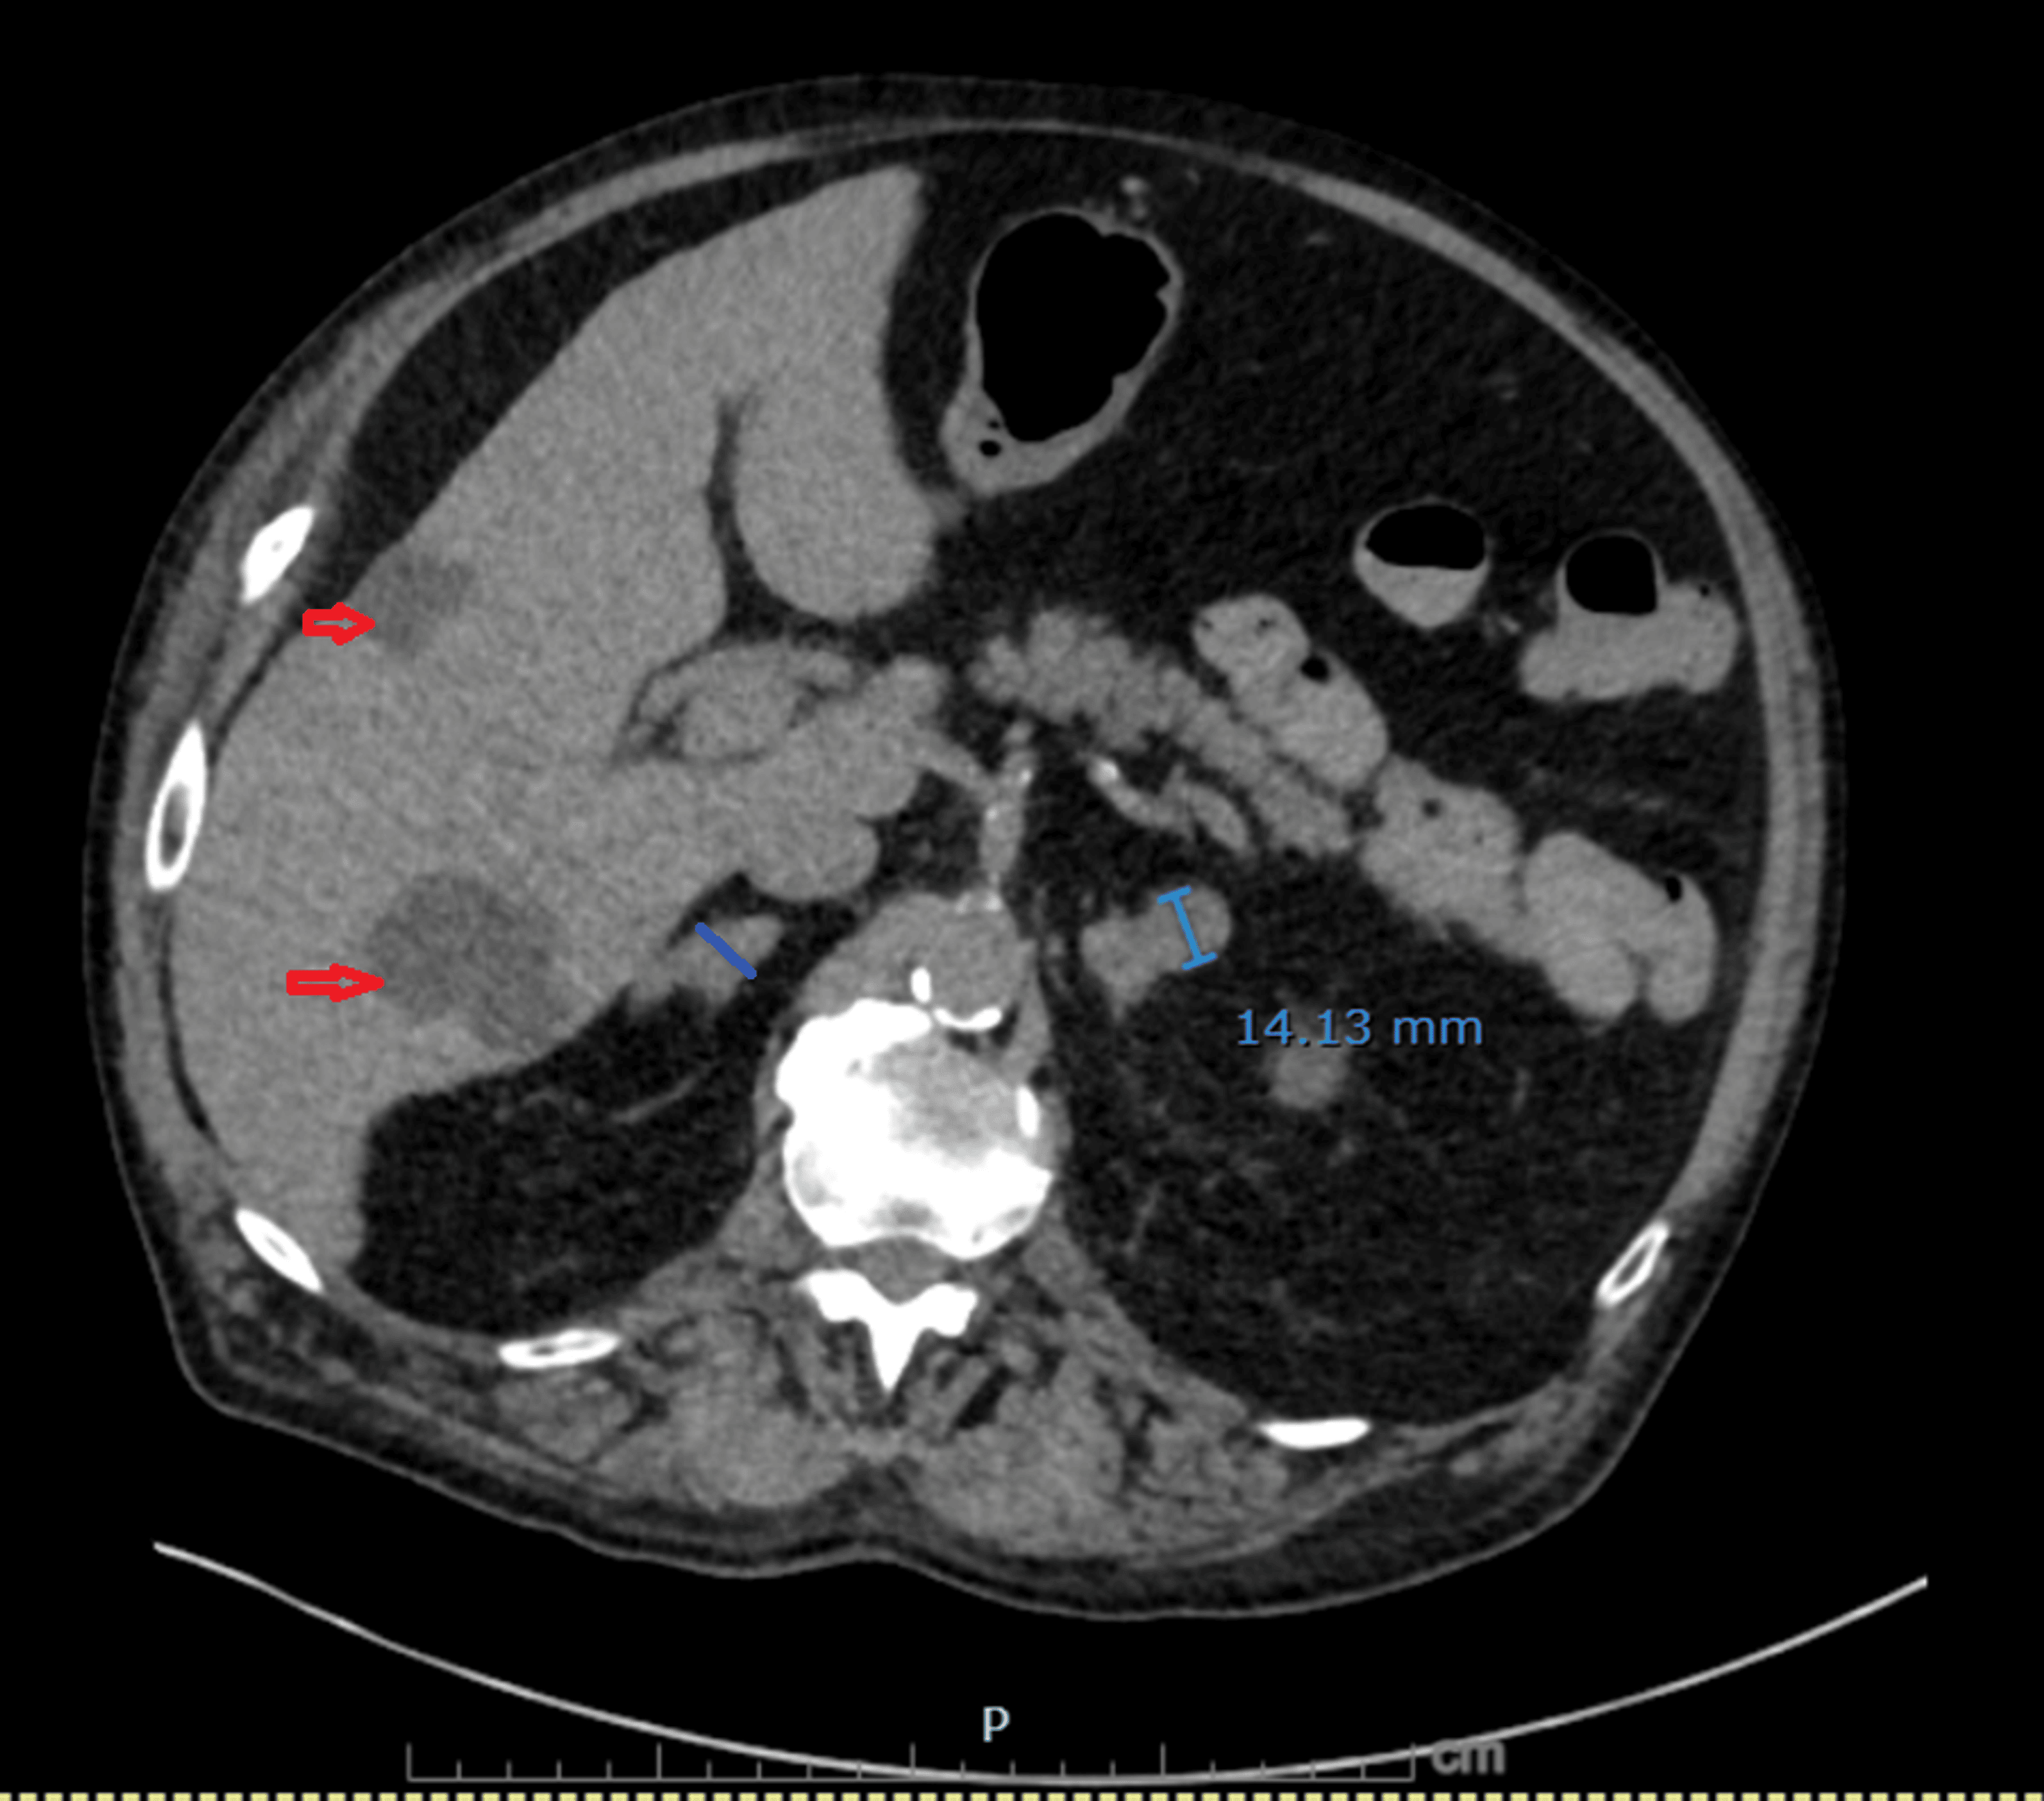

Figure 6: Non-contrast CT demonstrating bilateral adrenal metastases

Nodular enlargement of both adrenal glands has progressed compared with prior imaging: the left adrenal lateral limb measures 14 mm (previously 9.2 mm) and the right adrenal body measures 12.4 mm (previously 7 mm). Multiple benign hepatic cysts are also visualized (red arrows).